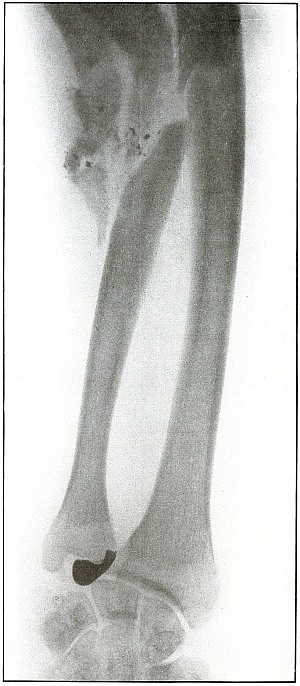

60. Gunshot fracture, tibia and fibula 130

61. Gunshot fracture, tibia and fibula 132

Rifle—Plate 60.

LOWER EXTREMITY.

Gunshot Fracture of the Tibia and Fibula,

with Lodgment of the Missile.

The course of the bullet was diagonal from within outward and backward about the middle of the leg, with the impact tangential on the tibia and direct on the fibula. The bullet lies just behind the tibia.

It is apparent that the bullet has been greatly deformed and that its jacket has been badly torn from the core. The force of impact on the object from which it ricocheted must have been contributed by the velocity of short range, which reduced the striking energy so greatly that the bullet was lodged by the resistance of the tibia and fibula.

The wound was not infected, and callus formation shows that repair has begun.

The treatment in such cases, without infection, is noninterference. The lodgment of the missile need not prejudicate the prognosis, and certainly the additional damage in the search for the bullet is not warranted, except under special indications. [Pg 132]